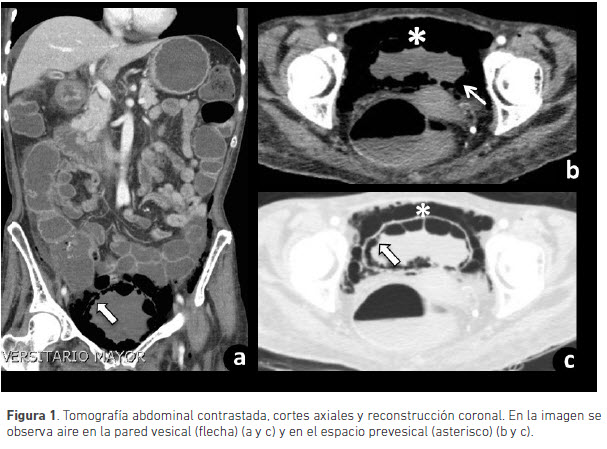

Debido a la enfermedad diarréica crónica se le realizó colonoscopia, en la cual se encontró pancolitis, así como una tomografía computarizada de abdomen en la que se evidenció aire en la pared vesical que se extendía a los tejidos blandos pélvicos y al retroperitoneo, compatible con cistitis enfisematosa (figuras 1 y 2).

Las alteraciones en la radiografía simple de abdomen incluyen un halo radiolúcido que delimita la pared vesical con o sin aire, en el área de proyección de la vejiga. La tomografía computarizada permite realizar el diagnóstico diferencial, logra una mayor caracterización de la distribución y extensión del aire. En ésta se identifican burbujas de aire en la pared vesical, el cual se puede extender al espacio perivesical, retroperitoneal, intraperitoneal y a tejido celular subcutáneo. Sólo se conoce de dos casos reportados con extensión del aire al espacio retroperitoneal (1,2).